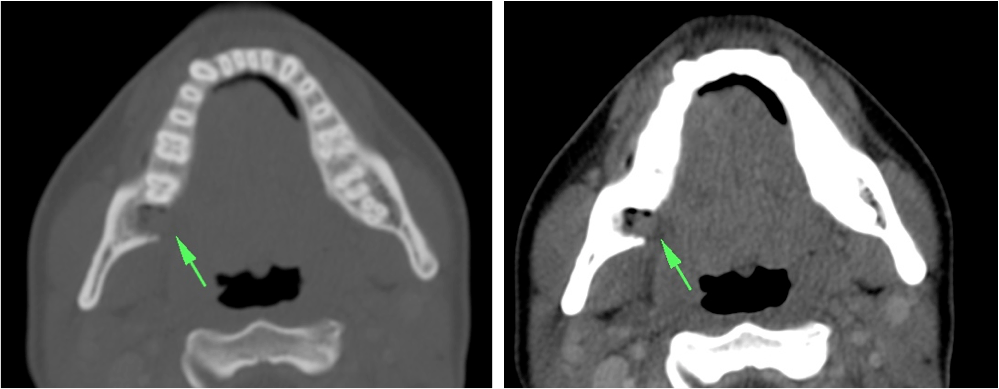

ESPACIO SUBLINGUAL Y SUBMANDIBULAR. ANGINA DE LUDWING:

Espacio sublingual:

Se sitúa inferior a la porción móvil de la lengua pero superior y medial al músculo milohioideo = Colecciones en esta localización son las denominadas sublinguales (las reconstrucciones coronales y sagitales son fundamentales). Contiene además a la glándula sublingual y una pequeña porción del aspecto superior de la glándula submandibular. Igual que en el espacio submandibular, las infecciones se manifiestan clínicamente por tumefacción, dolor, rubicundez y aumento de temperatura cervical. La mayoría son de origen dentario:

- Las que afectan a los dientes anteriores suelen limitarse al espacio sublingual, ya que sus raíces se quedan superior al milohiodeo.

- Las infecciones del 2º y 3º molar se suelen localizar en el espacio submandibular, ya que sus raíces se sitúan inferior a la inserción del milohioideo en la cara medial de la mandíbula (ver a continuación).

Espacio submandibular:

El espacio submandibular se sitúa inferior y lateral al músculo milohioideo. Es posterior al borde libre del milohioideo y comunica con el espacio sublingual (ver foto arriba). Contiene además la glándula submandibular, ganglios y a veces pueden localizarse quistes branquiales.

- Las infecciones del 2º y 3º molar se suelen localizar aquí. También pueden ser debidas a las supuración de adenopatías.

- Las infecciones de la glándula submandibular pueden confundirse con las de la parótida.

- Se produce aumento de tamaño, hiperdensidad e infiltración de la grasa adyacente. Cuando esto ocurre, se debe examinar el conducto de Wharton en busca de posibles cálculos.

- Otra forma de manifestación la constituye el flemón, con o sin celulitis y/o miositis, en estos casos se visualizan como masas hiperatenuadas, de bordes mal delimitados, con o sin engrosamiento e hiperatenuación de la musculatura, la piel y el tejido celular subcutáneo adyacentes.

Angina de Ludwing:

No es un absceso, es una celulitis multiespacial ya que afecta al suelo de la boca y los espacios sublingual y submandibular. Se manifiesta clínicamente por dolor, hinchazón, disfagia, fiebre y elevación de la lengua, puede asociar crepitación si se deben a microrganismos anaerobios. En la TC con contraste se observa:

- Realce y edema difuso de los componentes del suelo de la boca.

- Debe determinarse si existe colección susceptible de drenaje, permeabilidad de la vía aérea y presencia de aire secundario al crecimiento de microorganismos anaerobios.

- La infección causa elevación y desplazamiento de la lengua que puede cerrar la vía aérea (debe tenerse en cuenta a la hora de manejar estos pacientes antes de realizar la prueba).